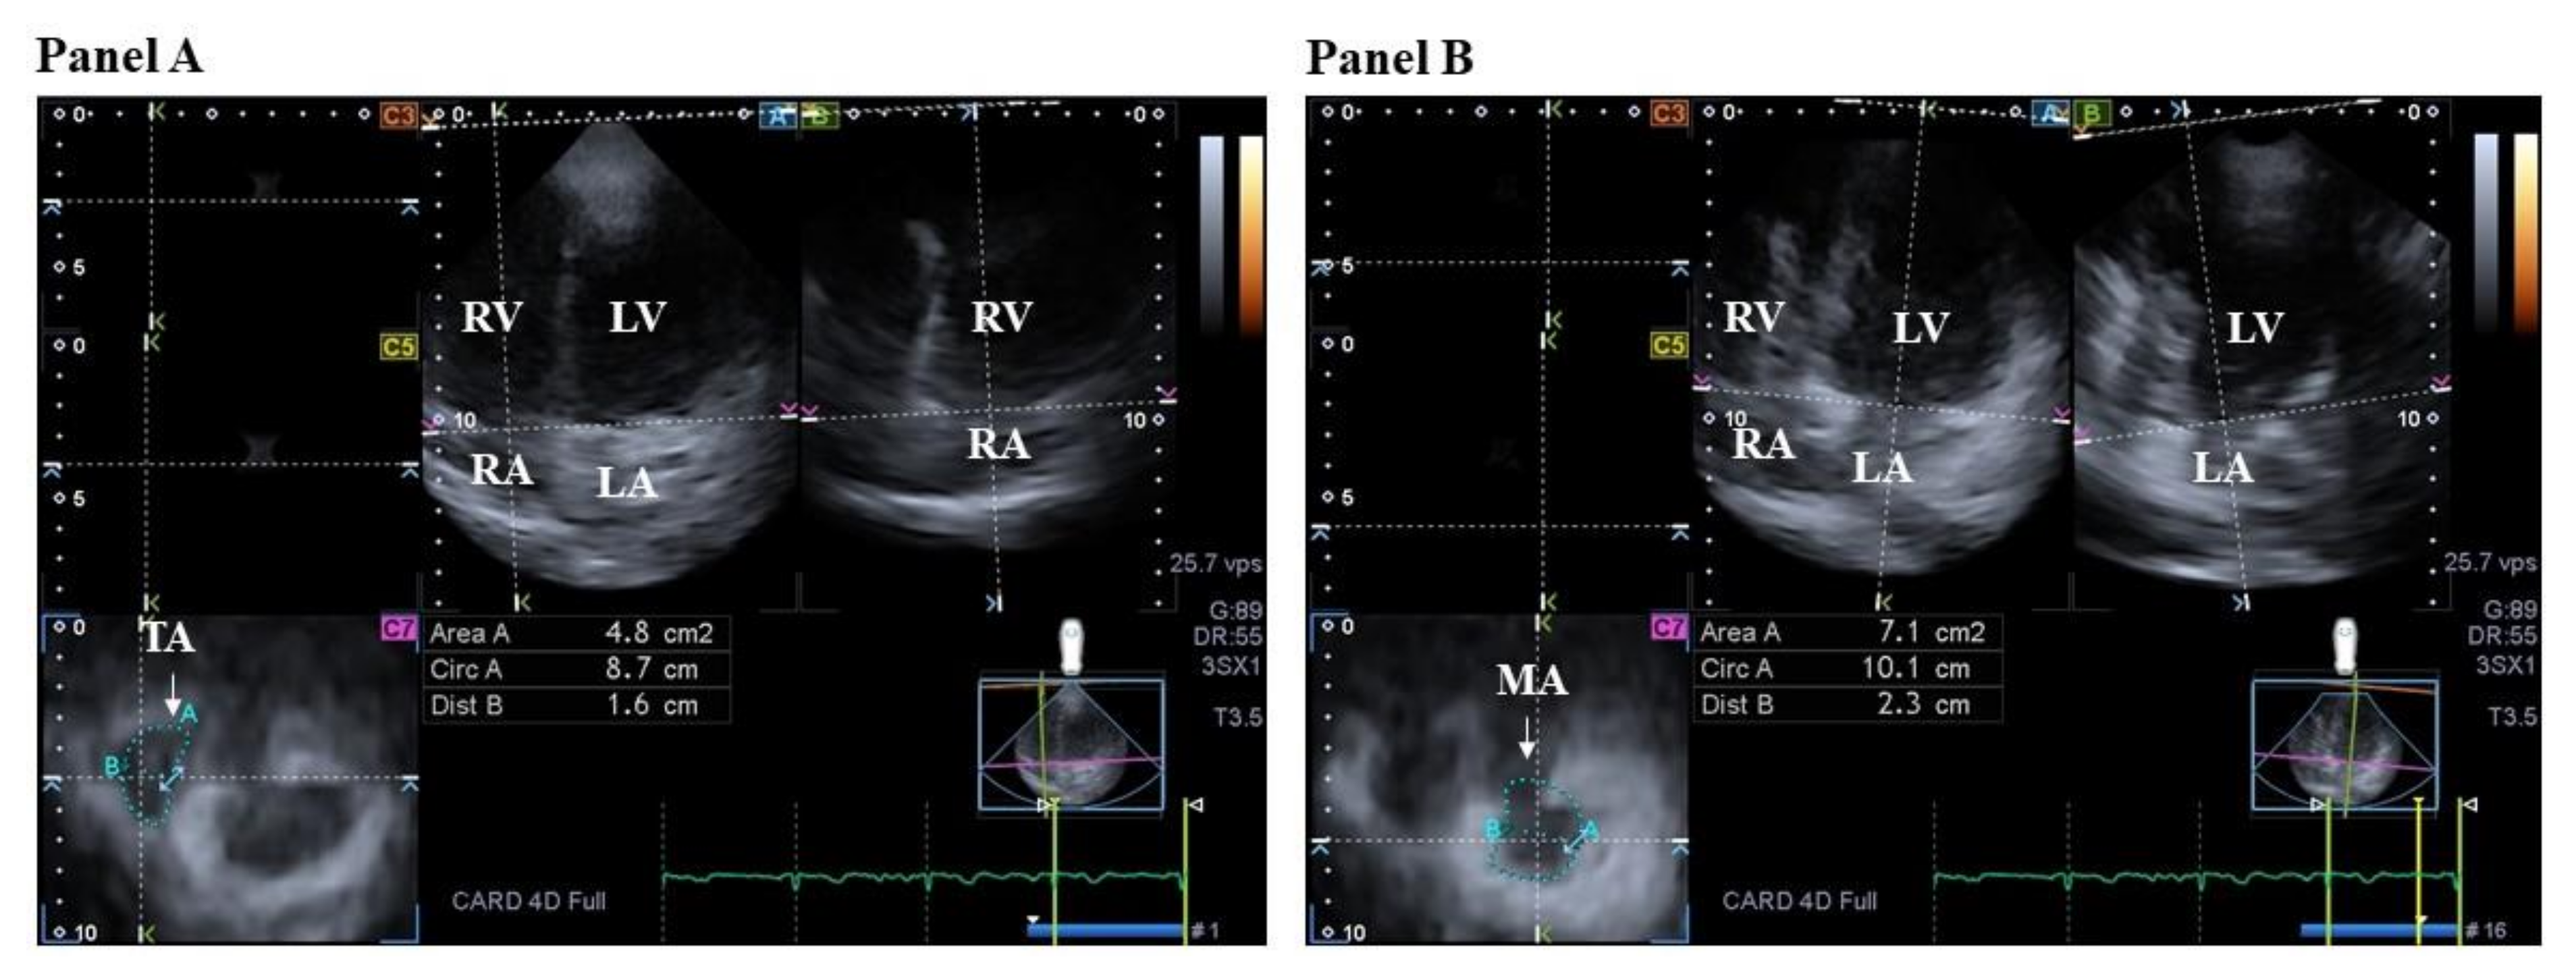

- Nemes, A.; Kormányos, Á.; Domsik, P.; Kalapos, A.; Lengyel, C.; Ambrus, N.; Valkusz, Z. Mitral annulus is dilated with preserved function in acromegaly regardless of its activity: Insights from the three-dimensional speckle-tracking echocardiographic MAGYAR-Path Study. Rev. Port. Cardiol. 2021, 40, 253–258. [Google Scholar] [CrossRef] [PubMed]